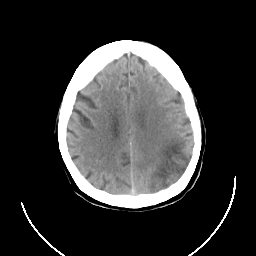

CT Study #3 -- Slice #20

[Home][Help][Clinical][Tour 1] Slice 20